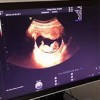

孕期产检必不可少,很多妈妈会走入一个误区,NT?唐筛?你搞清楚了吗?...

“排号四维彩超了,希望这次一定要预约上啊!”...